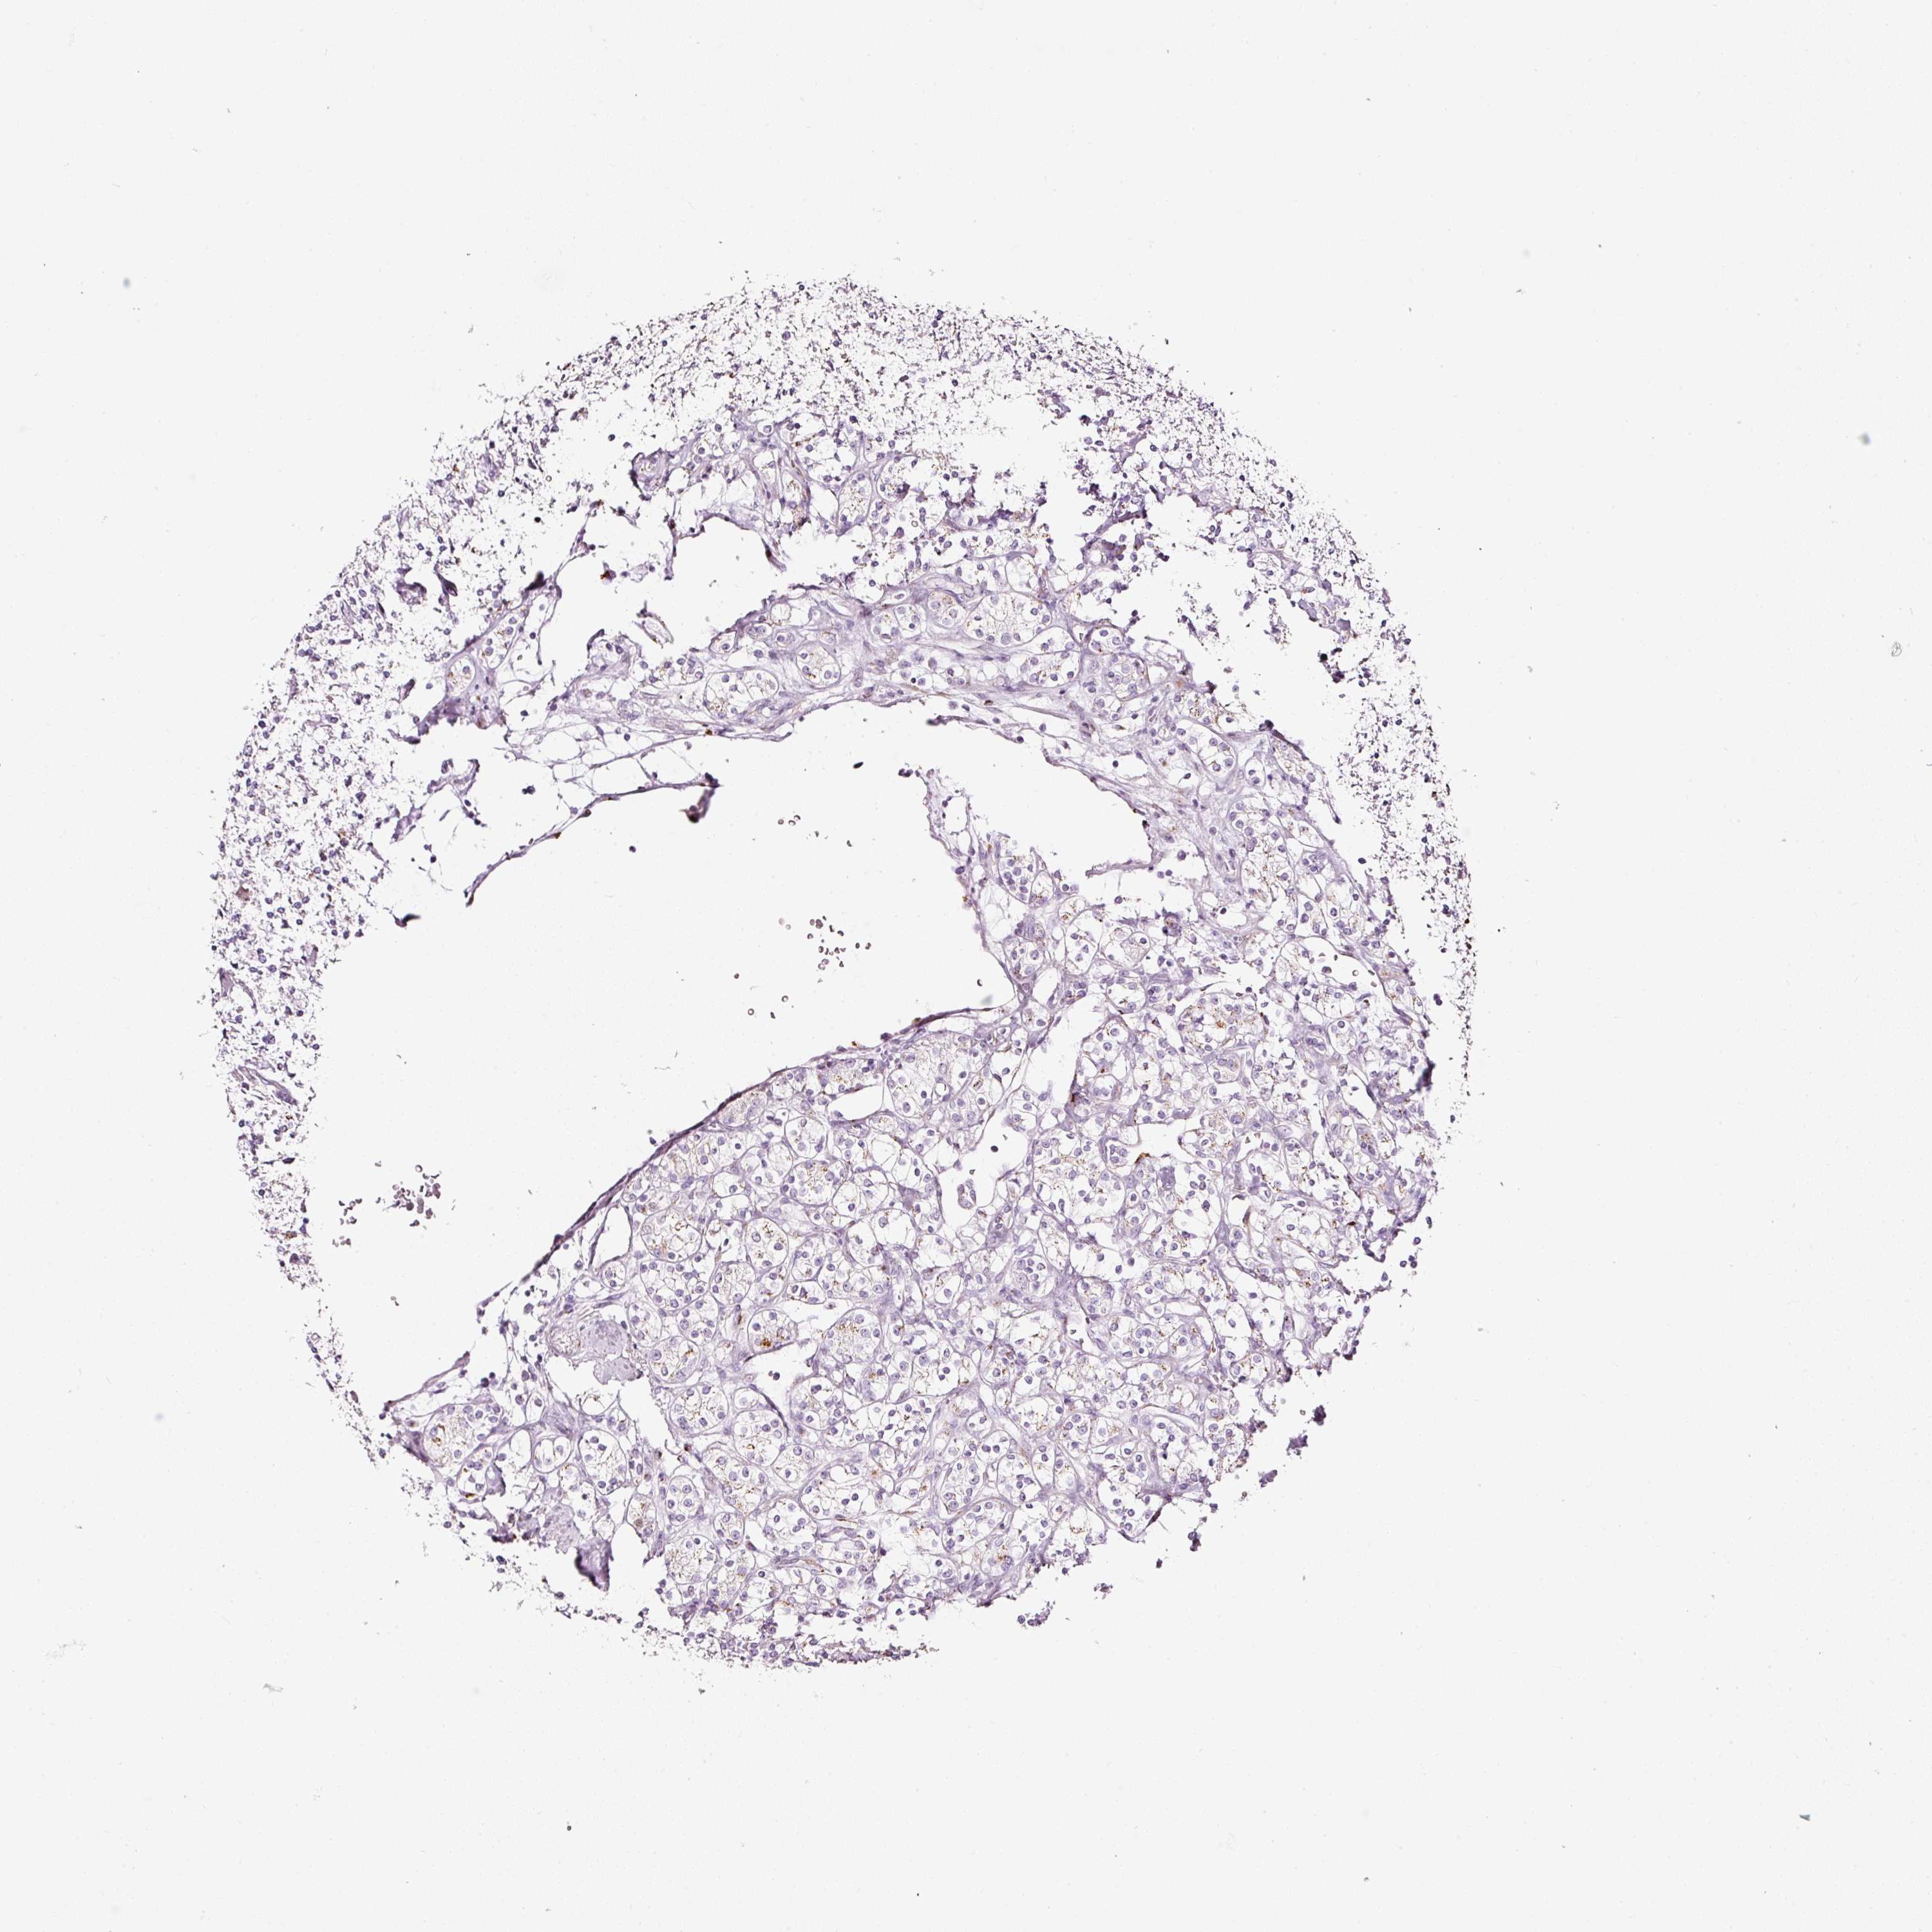

KIDNEY RENAL CLEAR CELL CARCINOMA (VALIDATION) - Interactive survival scatter ploti

The Survival Scatter plot shows the clinical status (i.e. dead or alive) for all individuals in the patient cohort, based on the same data that underlies the corresponding Kaplan-Meier plots. Patients that are alive at last time for follow-up are shown in blue and patients who have died during the study are shown in red.

The x-axis shows the expression levels (FPKM) of the investigated gene in the tumor tissue at the time of diagnosis. The y-axis shows the follow-up time after diagnosis (years). Both axes are complimented with kernel density curves demonstrating the data density over the axes. The top density plot shows the expression levels (FPKM) distribution among dead (red) and alive patients (blue). The right density plot shows the data density of the survived years of dead patients with high and low expression levels respectively, stratified using the cutoff indicated by the vertical dashed line through the Survival Scatter plot. This cutoff is automatically defined based on the FPKM cutoff that minimizes the p-score. The cutoff can be changed by dragging the vertical line or by entering a cutoff value in the square labeled "Current cut-off".

Under the Survival Scatter plot the p-score landscape (black curve; left axis) is shown together with dead median separation (red curve; right axis). Dead median separation is the difference in median mRNA expression between patients who have died with high and low expression, respectively. It is calculated as follows: median FPKM expression of dead patients with high expression - median FPKM expression of dead patients with low expression. This is intended to aid the user in visually exploring custom cutoffs and the associated p-scores and dead median separation.

Individual patient data is displayed and can be filtered by clicking on one or more of the category buttons on the top of the page. Categories describing expression level and patient information include: high, low, alive, dead, female, male and tumor stages. The scale of the x-axis can be toggled between linear and log-scale by clicking on the "x log" button. Mouse-over function shows TCGA ID, patient information and mRNA expression (FPKM) for each patient.

& Survival analysisi

Kaplan-Meier plots summarize results from analysis of correlation between mRNA expression level and patient survival. Patients were divided based on level of expression into one of the two groups "low" (under cut off) or "high" (over cut off). X-axis shows time for survival (years) and y-axis shows the probability of survival, where 1.0 corresponds to 100 percent.

SDF4 is not prognostic in Kidney Renal Clear Cell Carcinoma (validation)

Best expression cut offi

Based on the FPKM value of each gene, patients were classified into two groups and association between prognosis (survival) and gene expression (FPKM) was examined. The best expression cut-off refers the FPKM value that yields maximal difference with regard to survival between the two groups at the lowest log-rank P-value. Best expression cut-off was selected based on survival analysis .

When clicking on this number, the vertical dashed line indicating cut-off, the interactive survival plot, and the Kaplan-Meier curve will be adjusted to show results based on the best expression cut-off.

: 192.98

P scorei

Log-rank P value for Kaplan-Meier plot showing results from analysis of correlation between mRNA expression level and patient survival.

N/A

Average pTPM 167.3

Number of samples 100